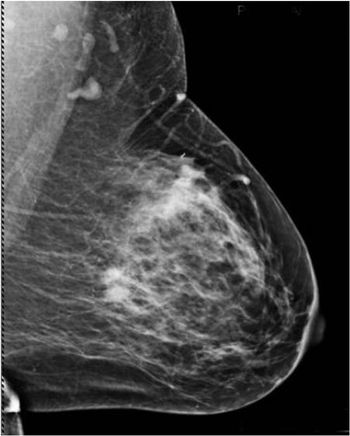

A 46-year-old patient presented for a second opinion on a mass found within the right breast on a prior outside mammogram. The patient denies any lumps or pain within either breast.